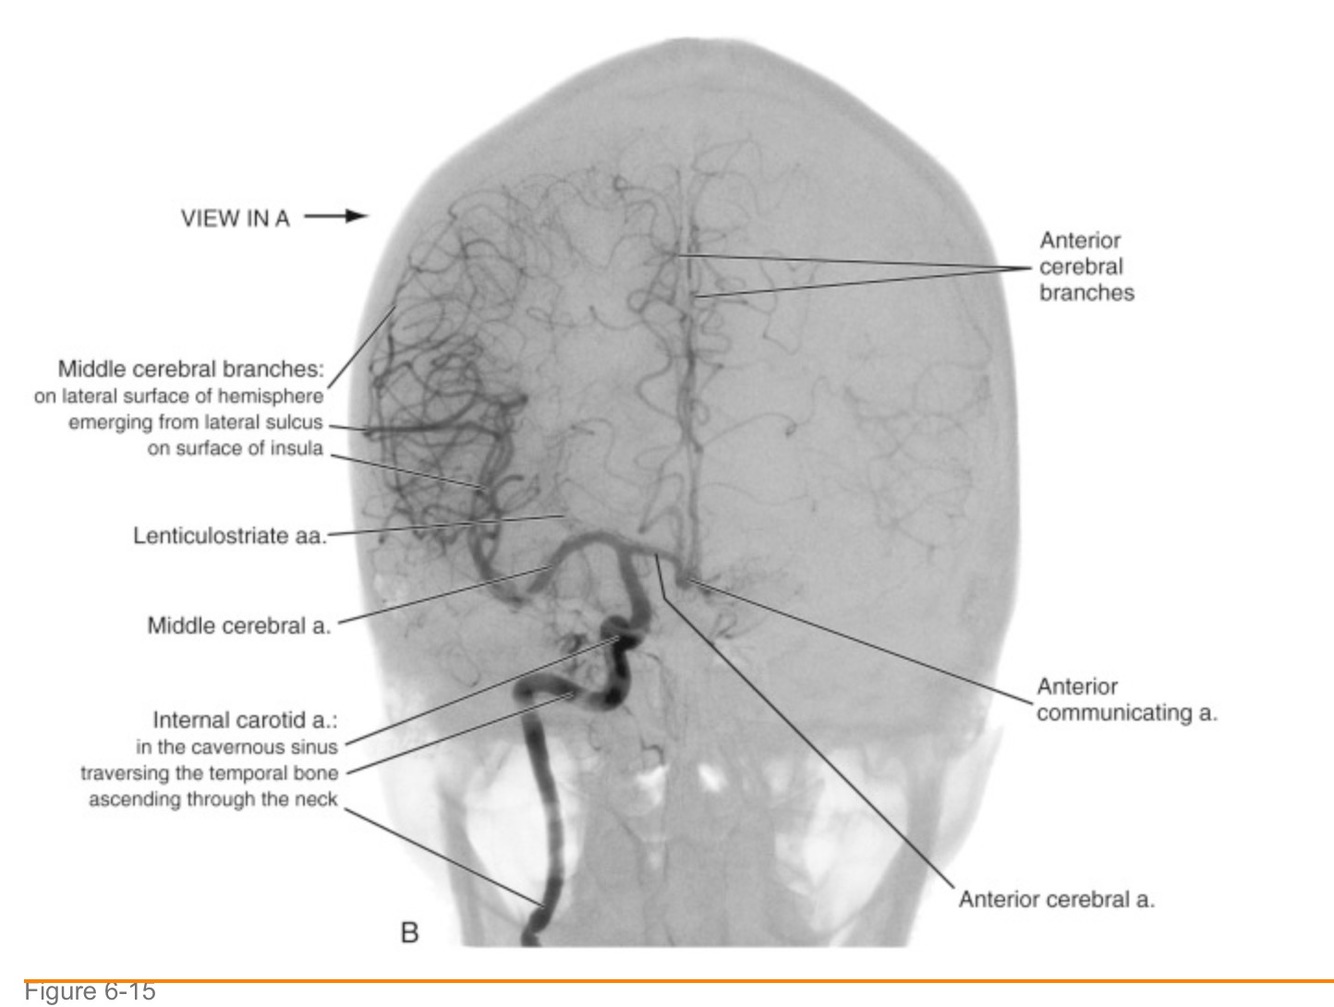

middle cerebral artery

– 2. What area of the brain does it supply?

– 3. What does this part of the brain do?

– 4. How will the patient present if these areas are damaged?

The majority of the hemisphere!